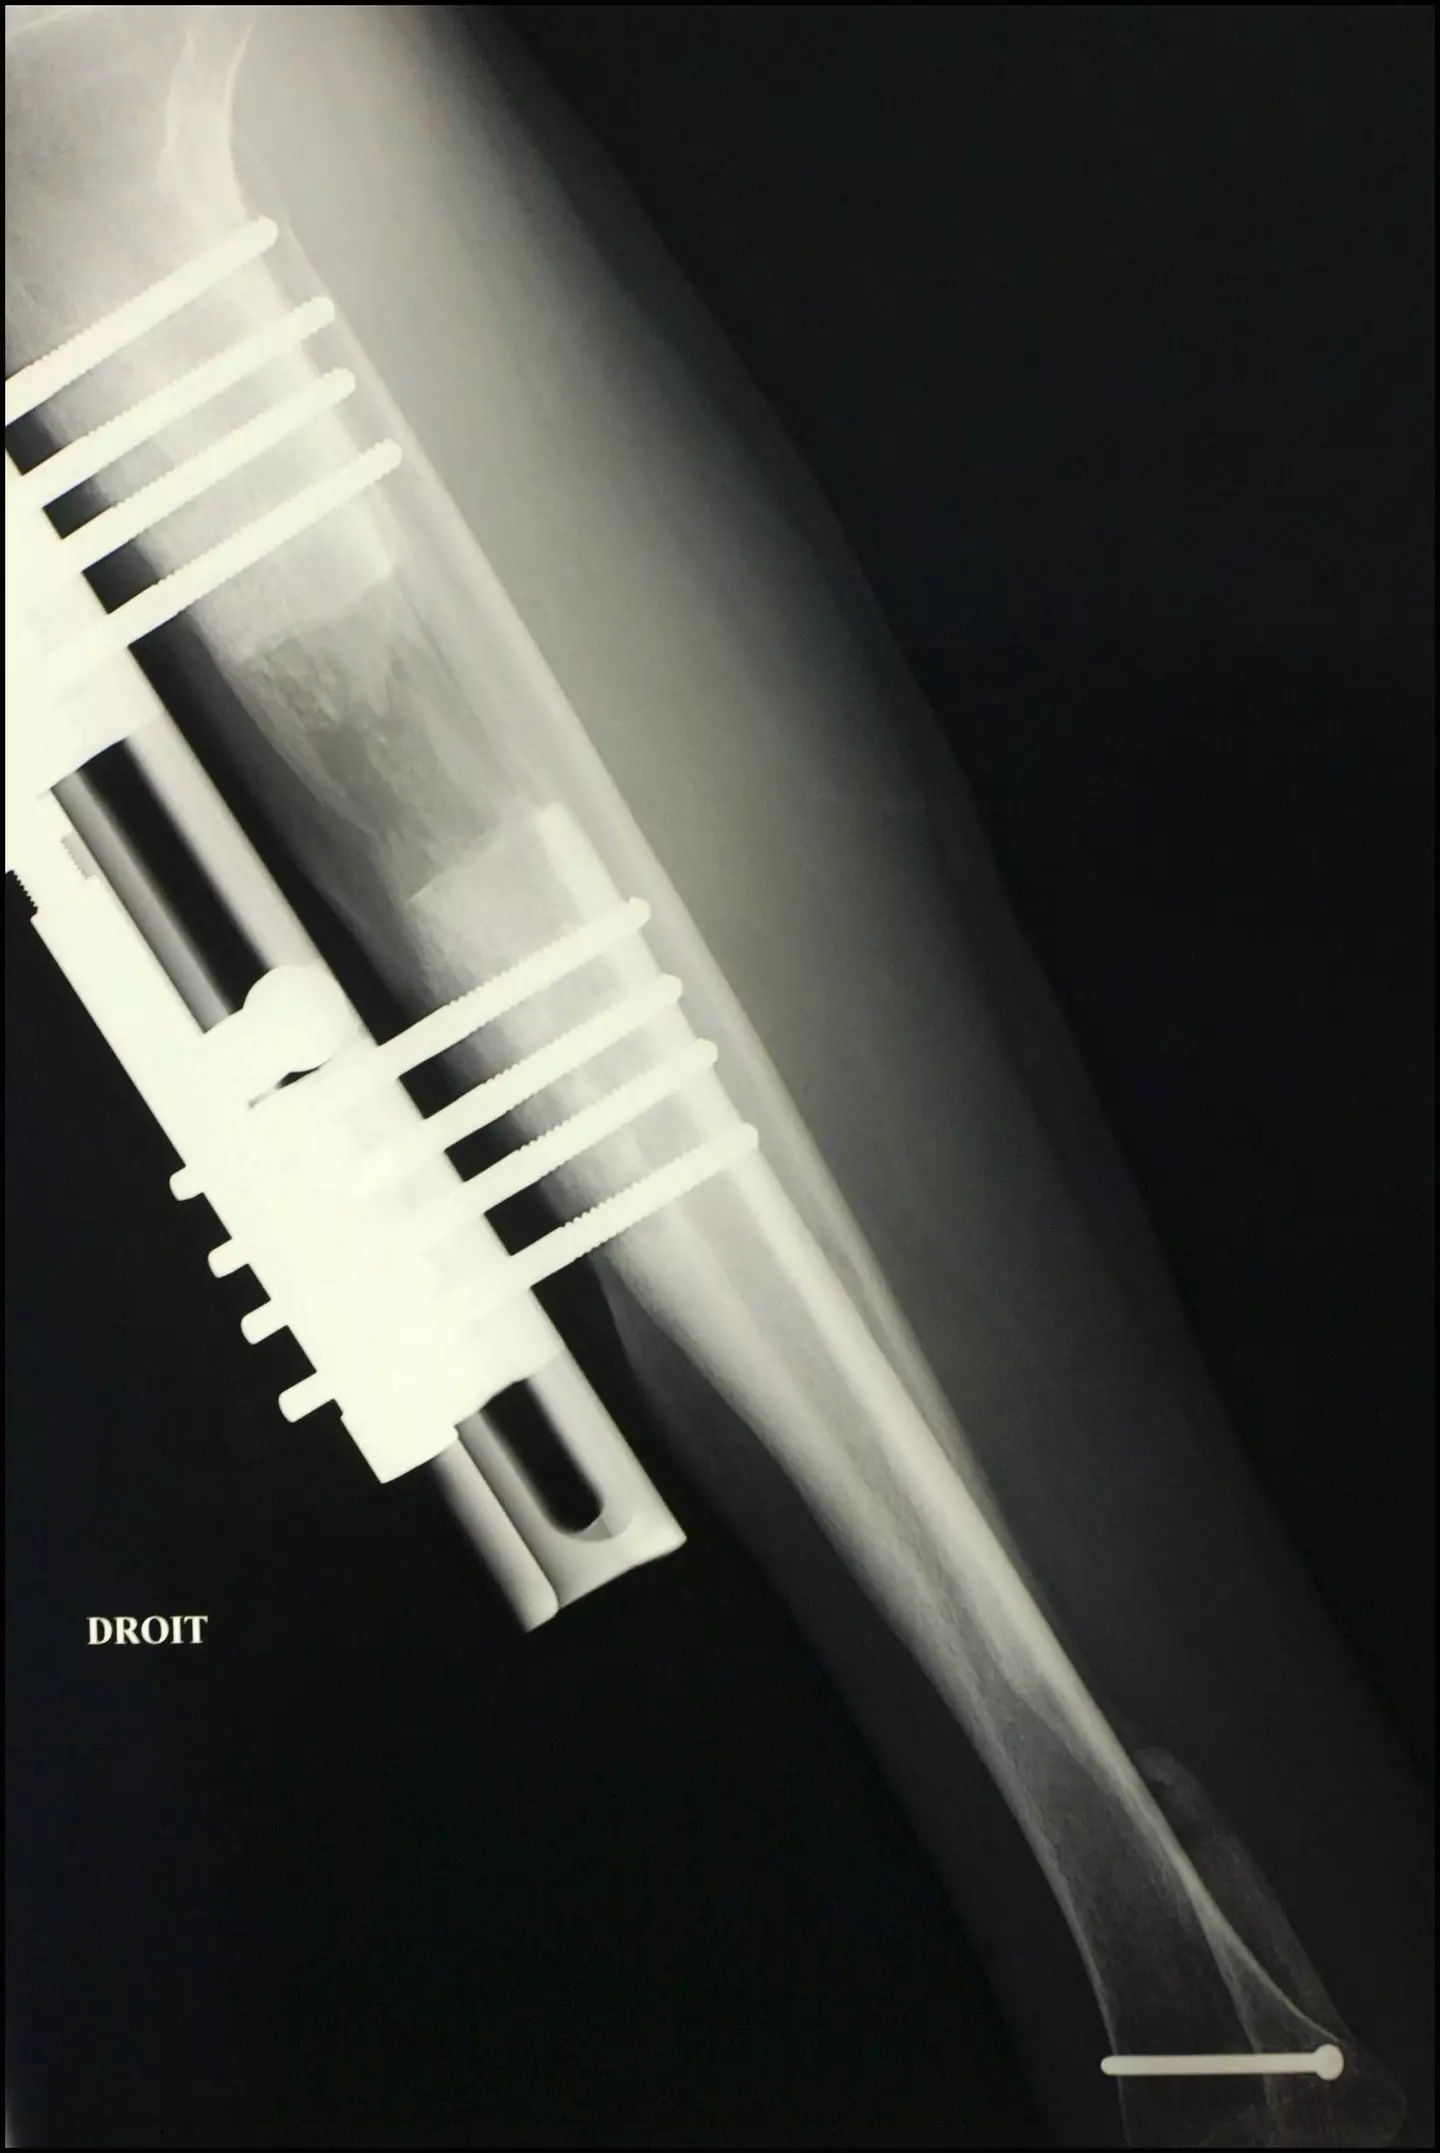

Things get off to a strong start when the bones in the thighs are broken. A series of metal pins and braces are then implanted to the area around the break with a little screw sticking out.

Over the next few weeks the patient has to turn the screw a set amount each day. This gradually stretches out the leg as the bone is healing.